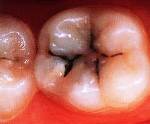

Кариес зубов и его последствия

Кариес зубов – довольно распространённое заболевание, при котором поражаются твёрдые ткани зуба. Кариес поражает не только зубы, но и приводит к ослаблению организма. В свою очередь при общих заболеваниях поражение зубов встречается значительно чаще.

Вначале поражается поверхность эмали зуба, появляется меловое пятно. Этот процесс протекает без боли, и, как правило, его не замечают. В этой стадии заболевание ещё можно остановить, если изменить режим питания, употреблять продукты, богатые витаминами и содержащие соли фосфора и кальция (творог, рыба, горох и др.), применять готовые препараты фосфора и кальция. В этот же период необходимо также местное лечение зубов – втирание специальных зубных паст, включающих фтор, фосфаты, кальций.Если заболевание зуба развивается, то под влиянием микробов ткани зуба начинают разрушаться и в коронке образуется дефект – полость. При этом могут появиться болевые ощущения: реакции на холодную, сладкую, солёную пищу и питьё. На этой стадии заболевания только пломбирование может спасти его от дальнейшего разрушения. Чем раньше оно будет сделано, тем лучше будут результаты лечения зубов.